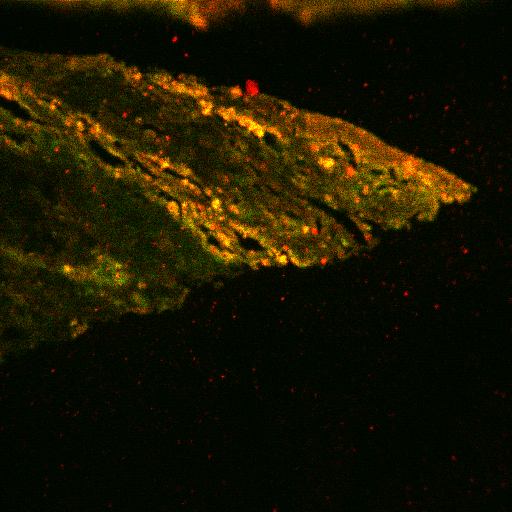

Figure 5. Dual labeling of surgically-excised inflammatory inactive CNV for CK 18 and MC

A: Inflammatory inactive CNV with pigmented cells at edge and fibrosis in stroma. (hematoxylin and eosin, 25x) B: Portion of CNV corresponding to that in Figure 4A showing dual labeling for CK18 and MCP corresponding to pigmented cells at edge, indicating RPE expression of MCP. (FITC, Texas red, 25x) C: Central area of CNV showing more fibrosis than inflammation in stroma. (hematoxylin and eosin, 25x) D: Area of CNV corresponding to Figure 4C showing dual labeling for CD68 and TF in rare stromal cells, indicating rare macrophages expressing TF. (FITC, TF, 63x) E: Negative control. (FITC, Texas red, 63x)